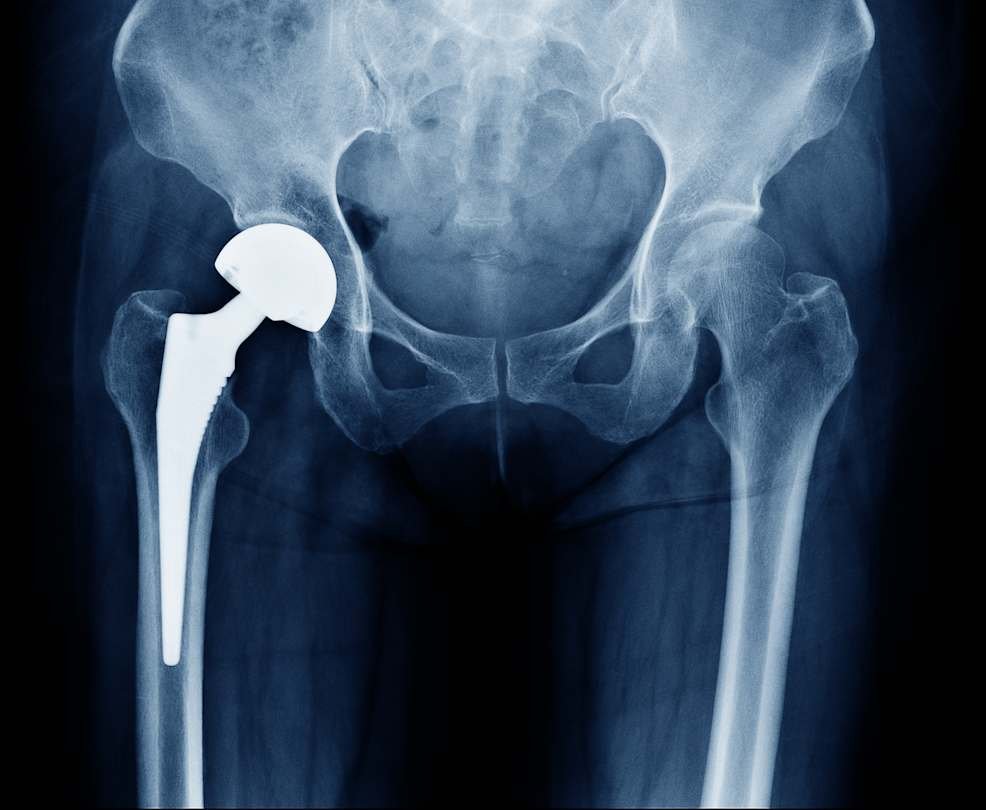

Doctors usually recommend hip replacement surgery only after nonsurgical treatments have not provided enough relief from the pain.

If those treatments no longer help, surgery may be considered—especially when pain and loss of function begin to affect daily life. “If the patient has done all of these things and is still feeling pain on a daily basis, especially at night with disturbed sleep, and if they have lost function that is affecting their daily activities, then surgery may be the best step,” he says.